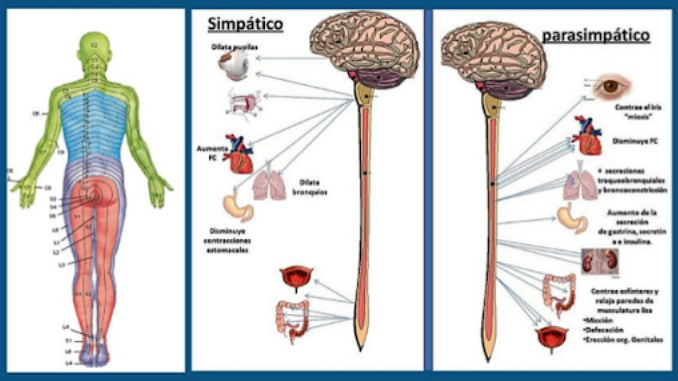

bEYİN bALANSI